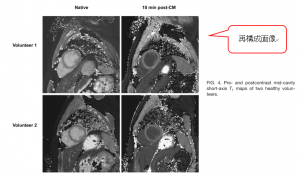

遅延造影像(LGE)画像の撮影前に、Inversion time決定のためLook-Lockerシークエンスを撮影する。Inversion pulseを入れたあとの心筋が時間経過とともに白→黒→白 と変化していくのを見ることができる。これは心筋のT1緩和の進行を時間経過とともに観察しているのだが、このLook-Lockerシークエンスを利用したのが現在最も広く用いられるMOLLI (MOdified Look-Locker Inversion recovery)というT1 mappingの撮像シークエンスである(下図4)[3] 。詳細は省くが、3回のInversion pulse(★)後、(青色の縦線のタイミングで)合計11枚の画像を撮影する。

次に、再構成画像を作る。Inversion pulse後の時間によって心筋のT1緩和の程度は異なるため、撮影された生の画像は、心筋が白や灰色や黒など、様々である(下図5) [4]。 この合計11枚のデータ(画像)をもとにピクセルごとのT1値の変化のグラフを描く。これは指数関数的なグラフになり、T1緩和時間(=T1値)は63%の回復に要する時間として求められる。ピクセルごとのT1緩和時間をもとめたものを1枚の画像に再構成する(下図5) [4]。